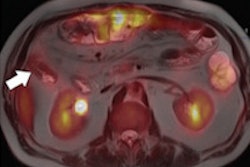

The new facility will be approximately 57,000 sq ft and will produce molybdenum-99, which decays into the diagnostic imaging agent technetium-99m. Technetium-99m is used in more than 40 million medical imaging procedures each year, primarily in stress tests to diagnose heart disease and in bone scans to stage cancer, Shine said.